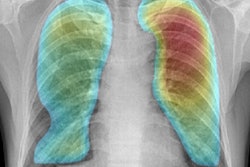

Even though Canada requires all new immigrants to undergo chest x-rays to screen for active tuberculosis, the researchers found that 87.3% of active cases came from just six countries: Afghanistan, China, India, Pakistan, the Philippines, and Vietnam. The x-rays didn't show a single case of active TB in immigrants from 179 other countries.